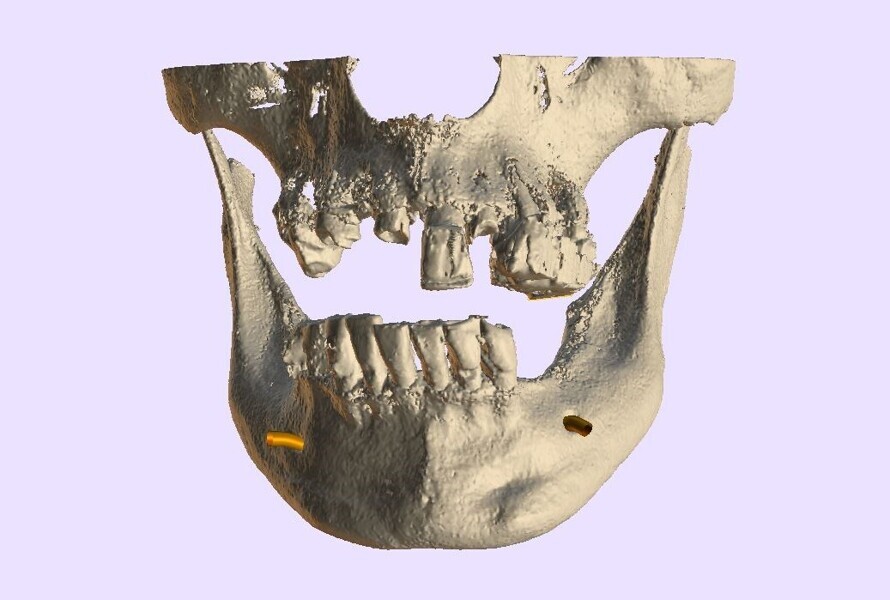

The planning continued with the examination and manipulation of the 3D reconstructed volume of the mandible and maxilla (Fig. 6a). Using the isolate function within the Blue Sky Plan software, the mandibular arch was separated from the maxillary arch, which with the merging of the intra-oral scanning data helped with the restoratively driven planning and refinement of implant positioning (Figs. 6b & c). The implants were then planned with precise regard for the emergence of the screw access channels represented by the yellow abutment projections which extended above the occlusal plane (Fig. 6d). Once each of the implant receptor sites and the vertical positions had been validated, the amount of alveolar reduction (after tooth extraction) was determined. A bone reduction guide was then designed with four anchor pins for stable fixation to the mandible (Fig. 7a). The various components of the diagnostic progress can be better appreciated using selective transparency to visualise structures based on their density (Fig. 7b). Selective transparency was again utilised to visualise the final location of the three central straight implants and the two angled implants, clearly indicating the safe proximity to the bilateral inferior alveolar nerves (Fig. 8a). The translucent STL model of the mandibular teeth and virtual teeth helped relate the implant positions to the restorative plan (Fig. 8b). The sequential osteotomy drilling guide was designed based upon the parameters of the implant system and guided drilling kit utilised. The osteotomy drilling guide was to be secured to the mandible with the same fixation pins as used for the bone reduction guide (Fig. 9).

Fig. 6a: 3D volumetric reconstruction of the maxilla and mandible.

Fig. 6b: The isolated mandibular arch.